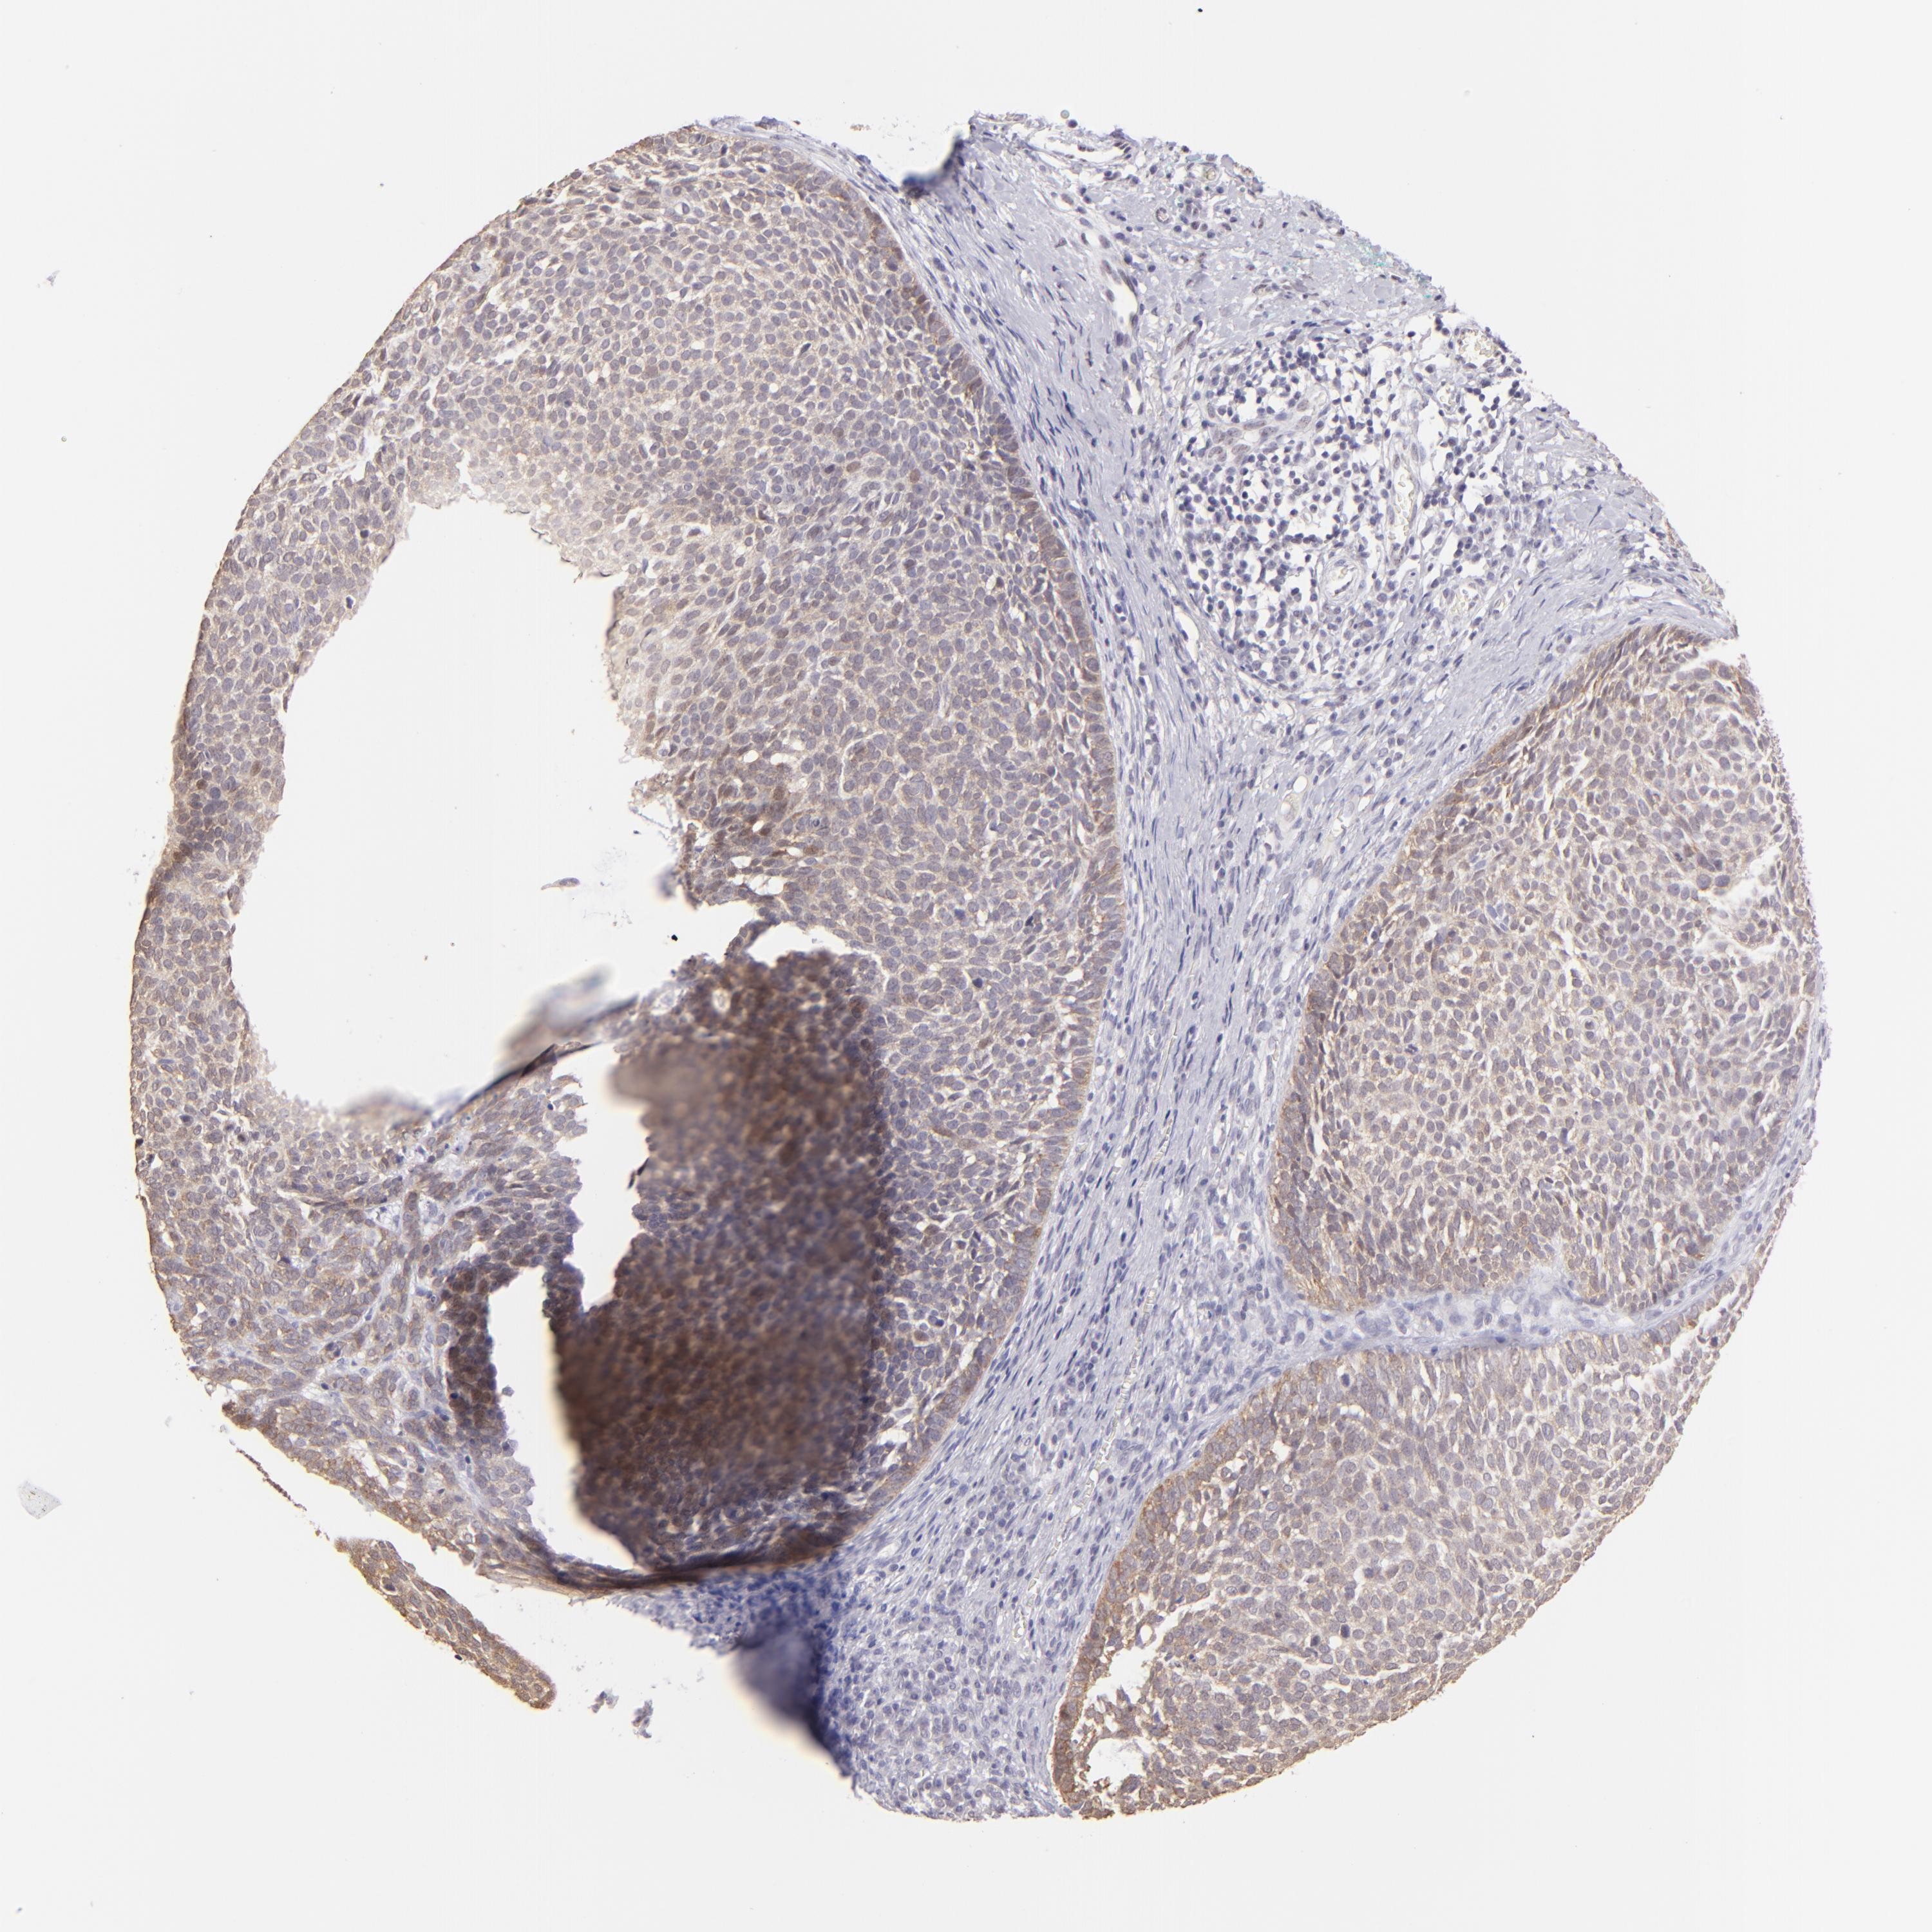

CANCER SKIN CANCER Show tissue menu

Basal cell and squamous cell cancer

SKIN CANCER - Protein expressioni

A mouse-over function shows sample information and annotation data. Click on an image to view it in a full screen mode. Samples can be filtered based on level of antibody staining by selecting one or several of the following categories: high, medium, low and not detected. The assay and annotation is described here.

Each image is clickable and will lead to virtual microscopy that enables deeper exploration of all samples and also displays staining intensity scores, fraction scores and subcellular localization as well as patient and tissue information for each sample.

Antibody CAB002620

Staining

High

Strong

Quantity

Location

Squamous cell carcinoma, NOS

Basal cell carcinoma